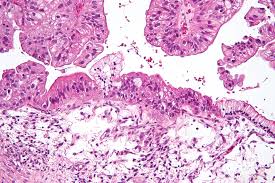

Ovarian Cancer Chapter 9 Gynaecological Oncology from static.cambridge.org It most often occurs in women in their 50s and beyond. Ovarian cancer is the fourth leading cause of cancer death among women. Thus, it is important to keep track of your health and compare this. Though unexplained fatigue can also be caused by anemia, diabetes and many other conditions, any gynecological cancer can cause it. Ovarian cancer starts in women's ovaries and often spreads to other parts of their body. For years, the cancer risks involved with using hormone replacement therapy divided the medical community. Increased exposure to hormones, such as estrogen increased number of ovulations ovulation occurs when the ovary releases eggs. Pay attention, trust your intuition and do not hesitate to ask your doctor for further investigation!